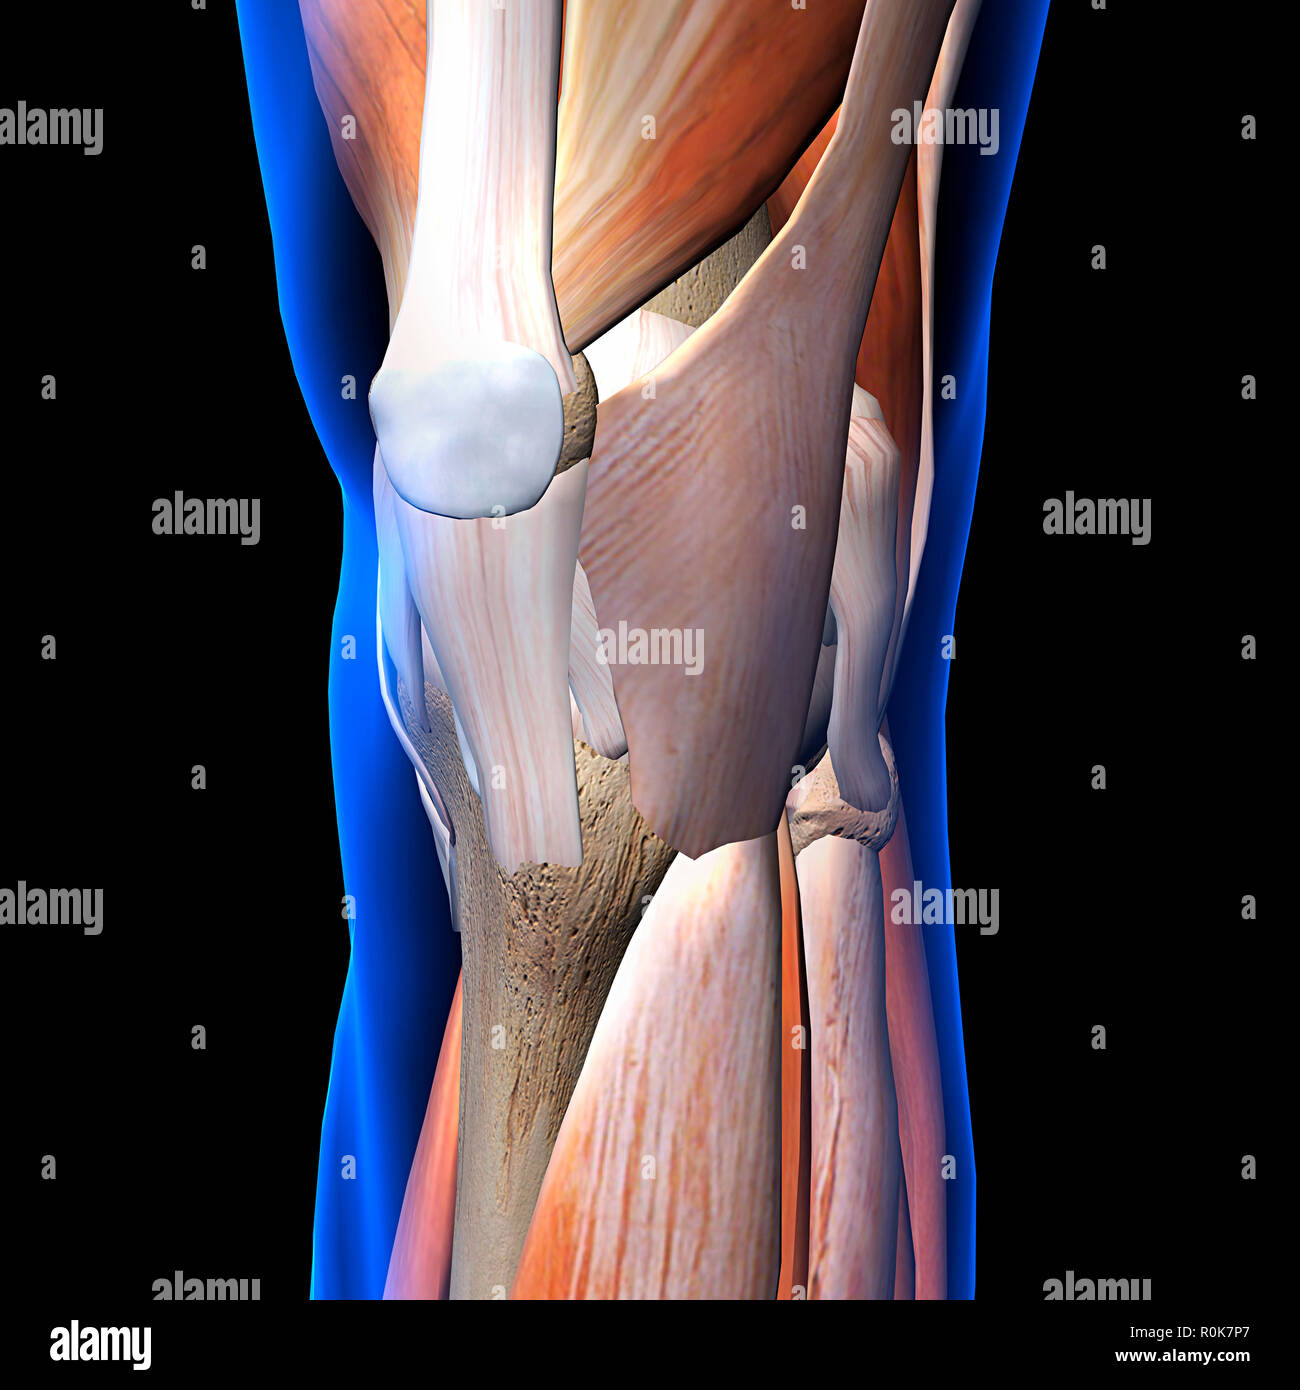

Knee muscles and ligaments, x-ray view on black background. Stock Photohttps://www.alamy.com/image-license-details/?v=1https://www.alamy.com/knee-muscles-and-ligaments-x-ray-view-on-black-background-image224157983.html

Knee muscles and ligaments, x-ray view on black background. Stock Photohttps://www.alamy.com/image-license-details/?v=1https://www.alamy.com/knee-muscles-and-ligaments-x-ray-view-on-black-background-image224157983.htmlRFR0K7P7–Knee muscles and ligaments, x-ray view on black background.